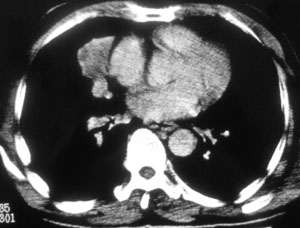

性别 男  62岁 因咳嗽及左肱骨剧烈痛疼数天来院检查。

右中央型肺癌并肱骨转移。

考虑右肺中叶肺癌并左肱骨转移伴病理性骨折。

支持右肺中心型肺癌并肺内及左肱骨转移伴病理性骨折

右肺中心型肺癌并中叶不张,左肱骨溶骨性转移并病理骨折。